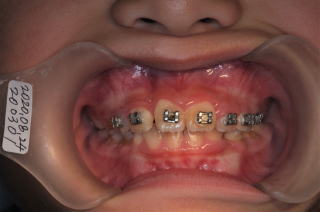

2020年03月23日

反対咬合の歯にブラケットセット